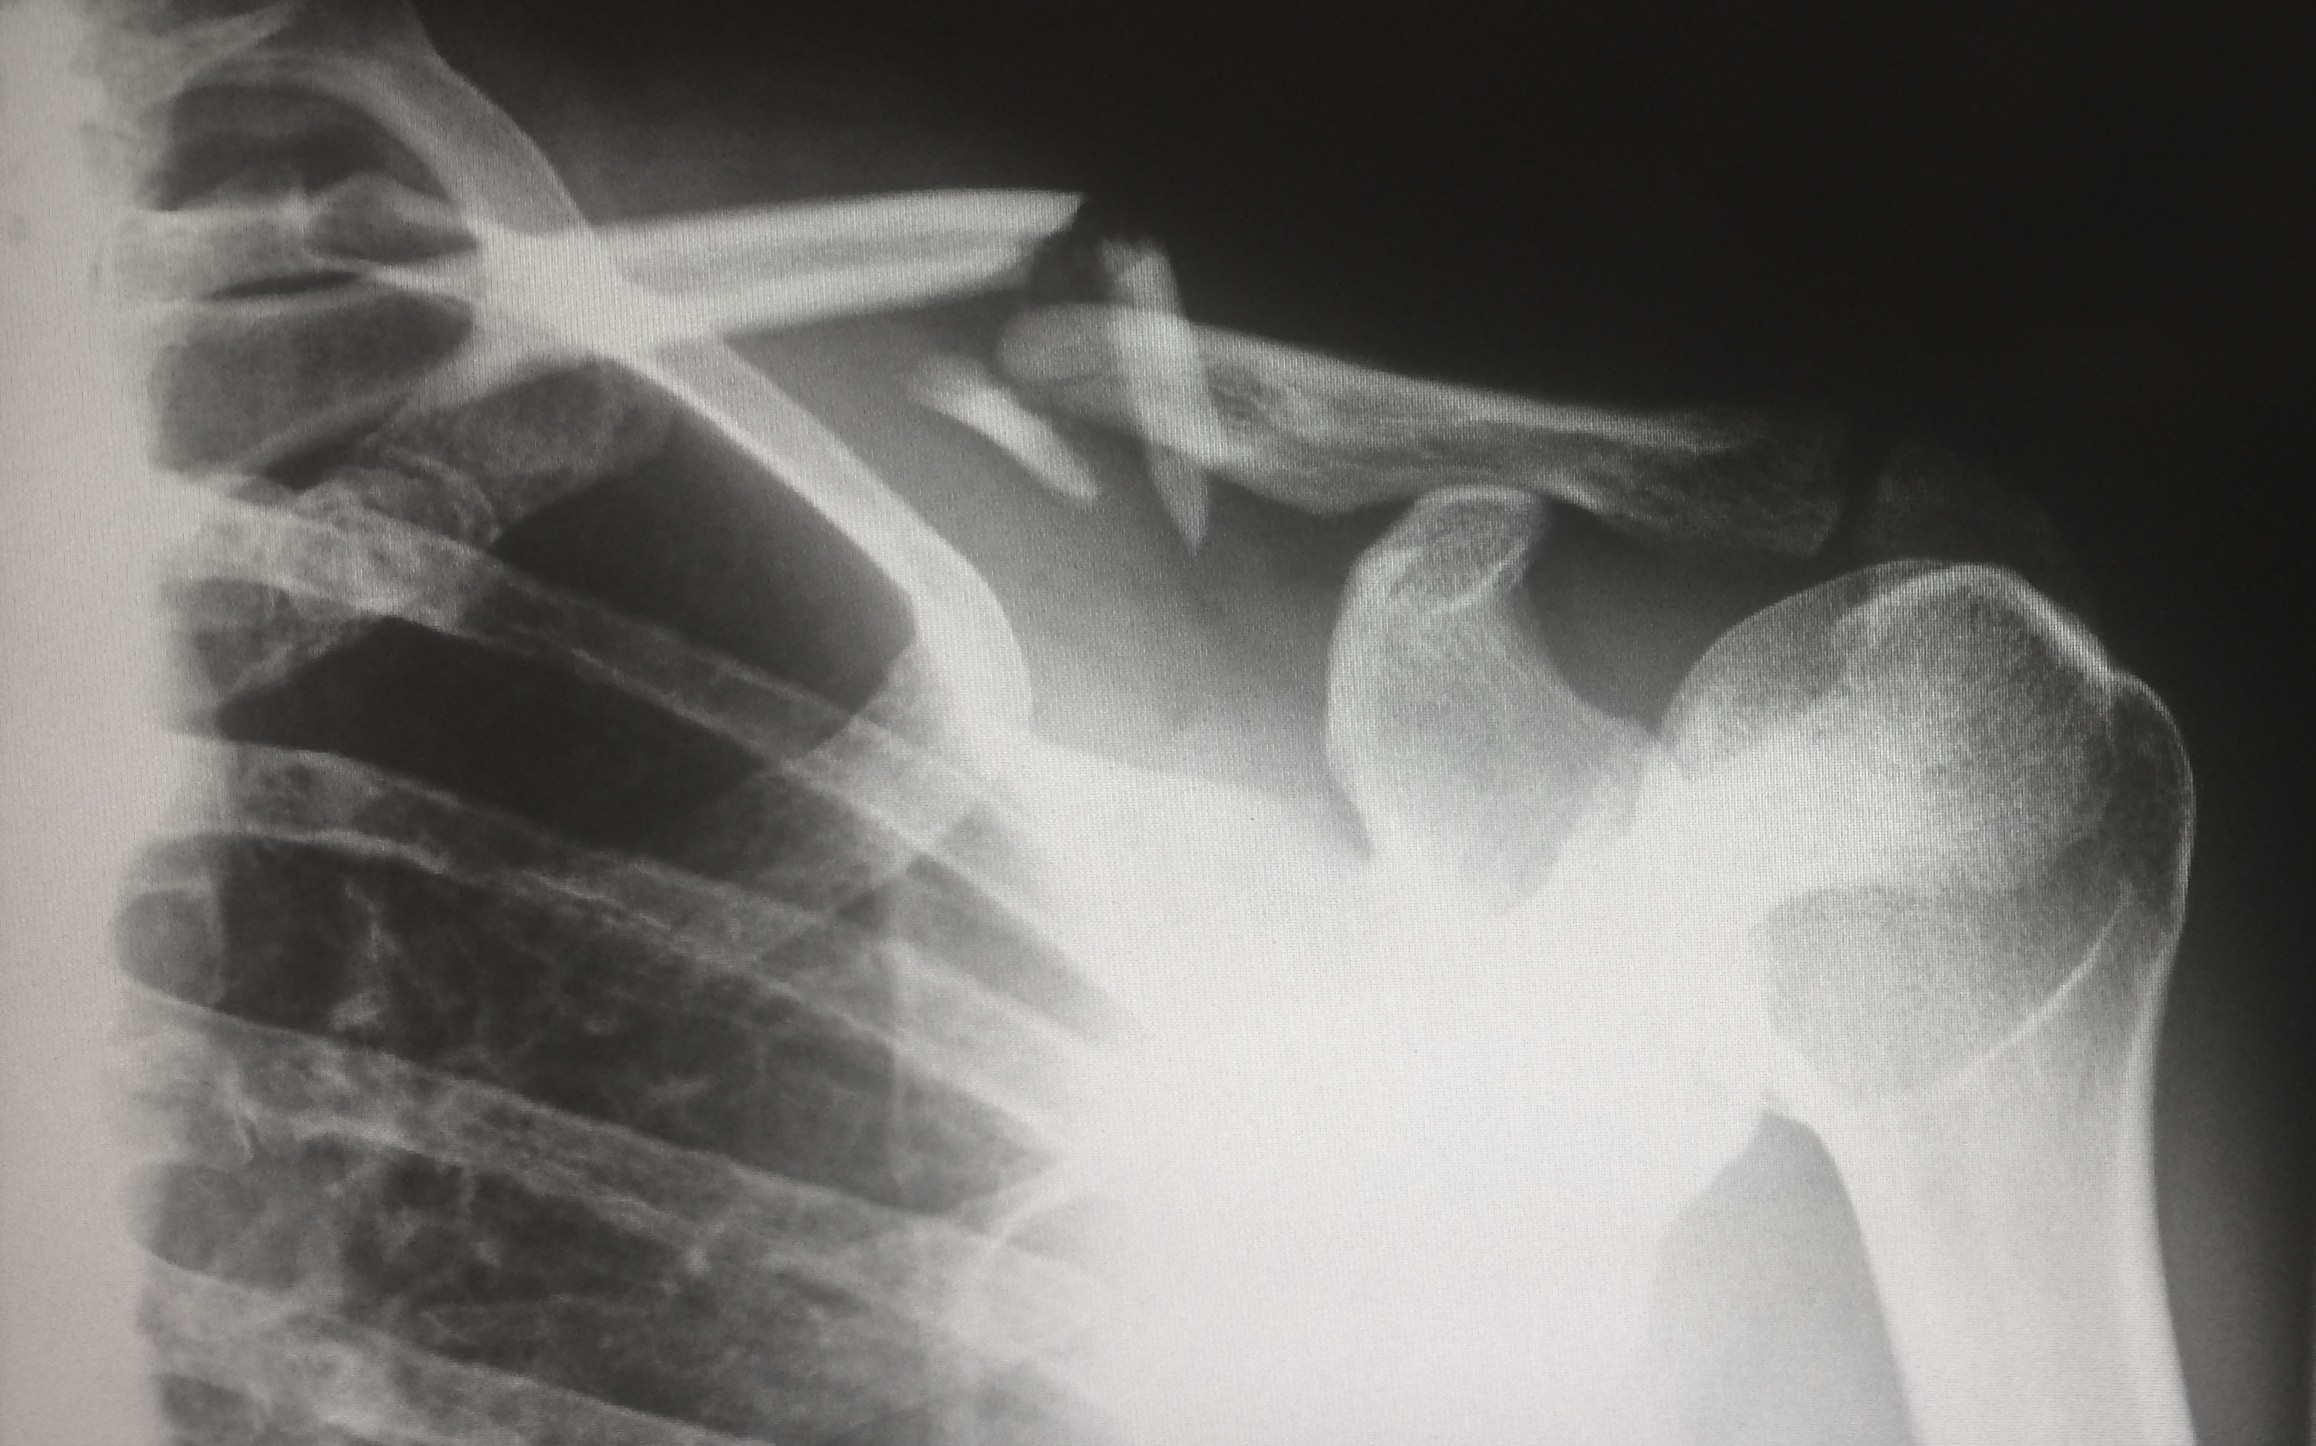

1. See a Doctor

No matter what kind of injuries you have sustained or the perceived scale of those injuries, the first thing that any injured person must do is to see a doctor. The doctor will help you to detect the internal injuries that aren’t visible from the outside, and they’ll even help you to correctly judge the impact of these injuries. Many injuries like whiplash, concussion, and internal bleeding aren’t detectable by an untrained person, but a doctor knows exactly what to look out for. Your health is the most important thing in any case, and you should not ignore it at any cost. The doctor will also help document the damage, which makes your insurance claims easier.